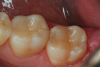

A 66 year-old female patientpresented with a "stained" occlusal groove in tooth No. 13 that did not "stick" with an explorer tip (Figure 1).  Upon radiographic examination (Figure 2), a rather large carious lesion was discovered that encroached upon the dental pulp.  There were no other clinical or subjective signs to alert the clinician or patient to the extent of the damage that had already occurred in the tooth. Figure 3 through Figure 5 show selective caries removal using a round end plastic polymer bur (SmartBurII, SS White).  Before caries removal, isolation of the operative quadrant was achieved using Isovac (Zyris). Because of its Knoop hardness of 90, SmartBurII allows for removal of infected dentin only, while allowing affected dentin to remain for potential remineralization with a bioactive liner or base material.

Fig 1.	A preoperative occlusal view of tooth No. 13 that has a “stain” in the occlusal groove that does not “stick” with an explorer.

Figure 1